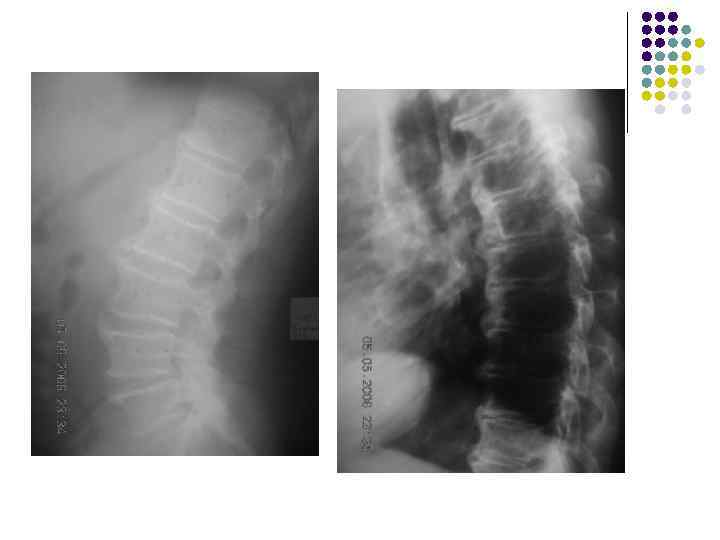

l На рентгенограмме грудного отдела позвоночного столба в боковой проекции определяются признаки выраженных, распространенных дистрофических изменений в виде болезни Форестье за счет характерных костных разрастаний под передней продольной связкой практически во всех визуализированных отделах грудной части позвоночника. На этом фоне отмечаются также явления умеренного и также распространенного отсеохондроза – сужение межпозвонковых простанств, субхондральный остеосклероз, соответствующие костные разрастания. Положение тел позвонков правильное, деструктивных изменений нет.